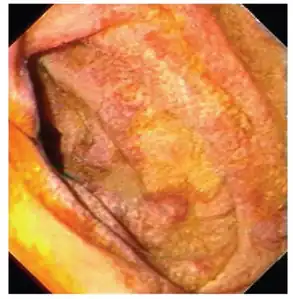

Endoscopy of the duodenum and jejunum can reveal pale yellow shaggy mucosa with erythematous eroded patches in patients with classic intestinal Whipple's disease, and small bowel X-rays may show some thickened folds. Other pathological findings may include enlarged mesenteric lymph nodes, hypercellularity of lamina propria with "foamy macrophages", and a concurrent decreased number of lymphocytes and plasma cells, per high power field view of the biopsy.

- Mucosa is swollen and grey-yellowish